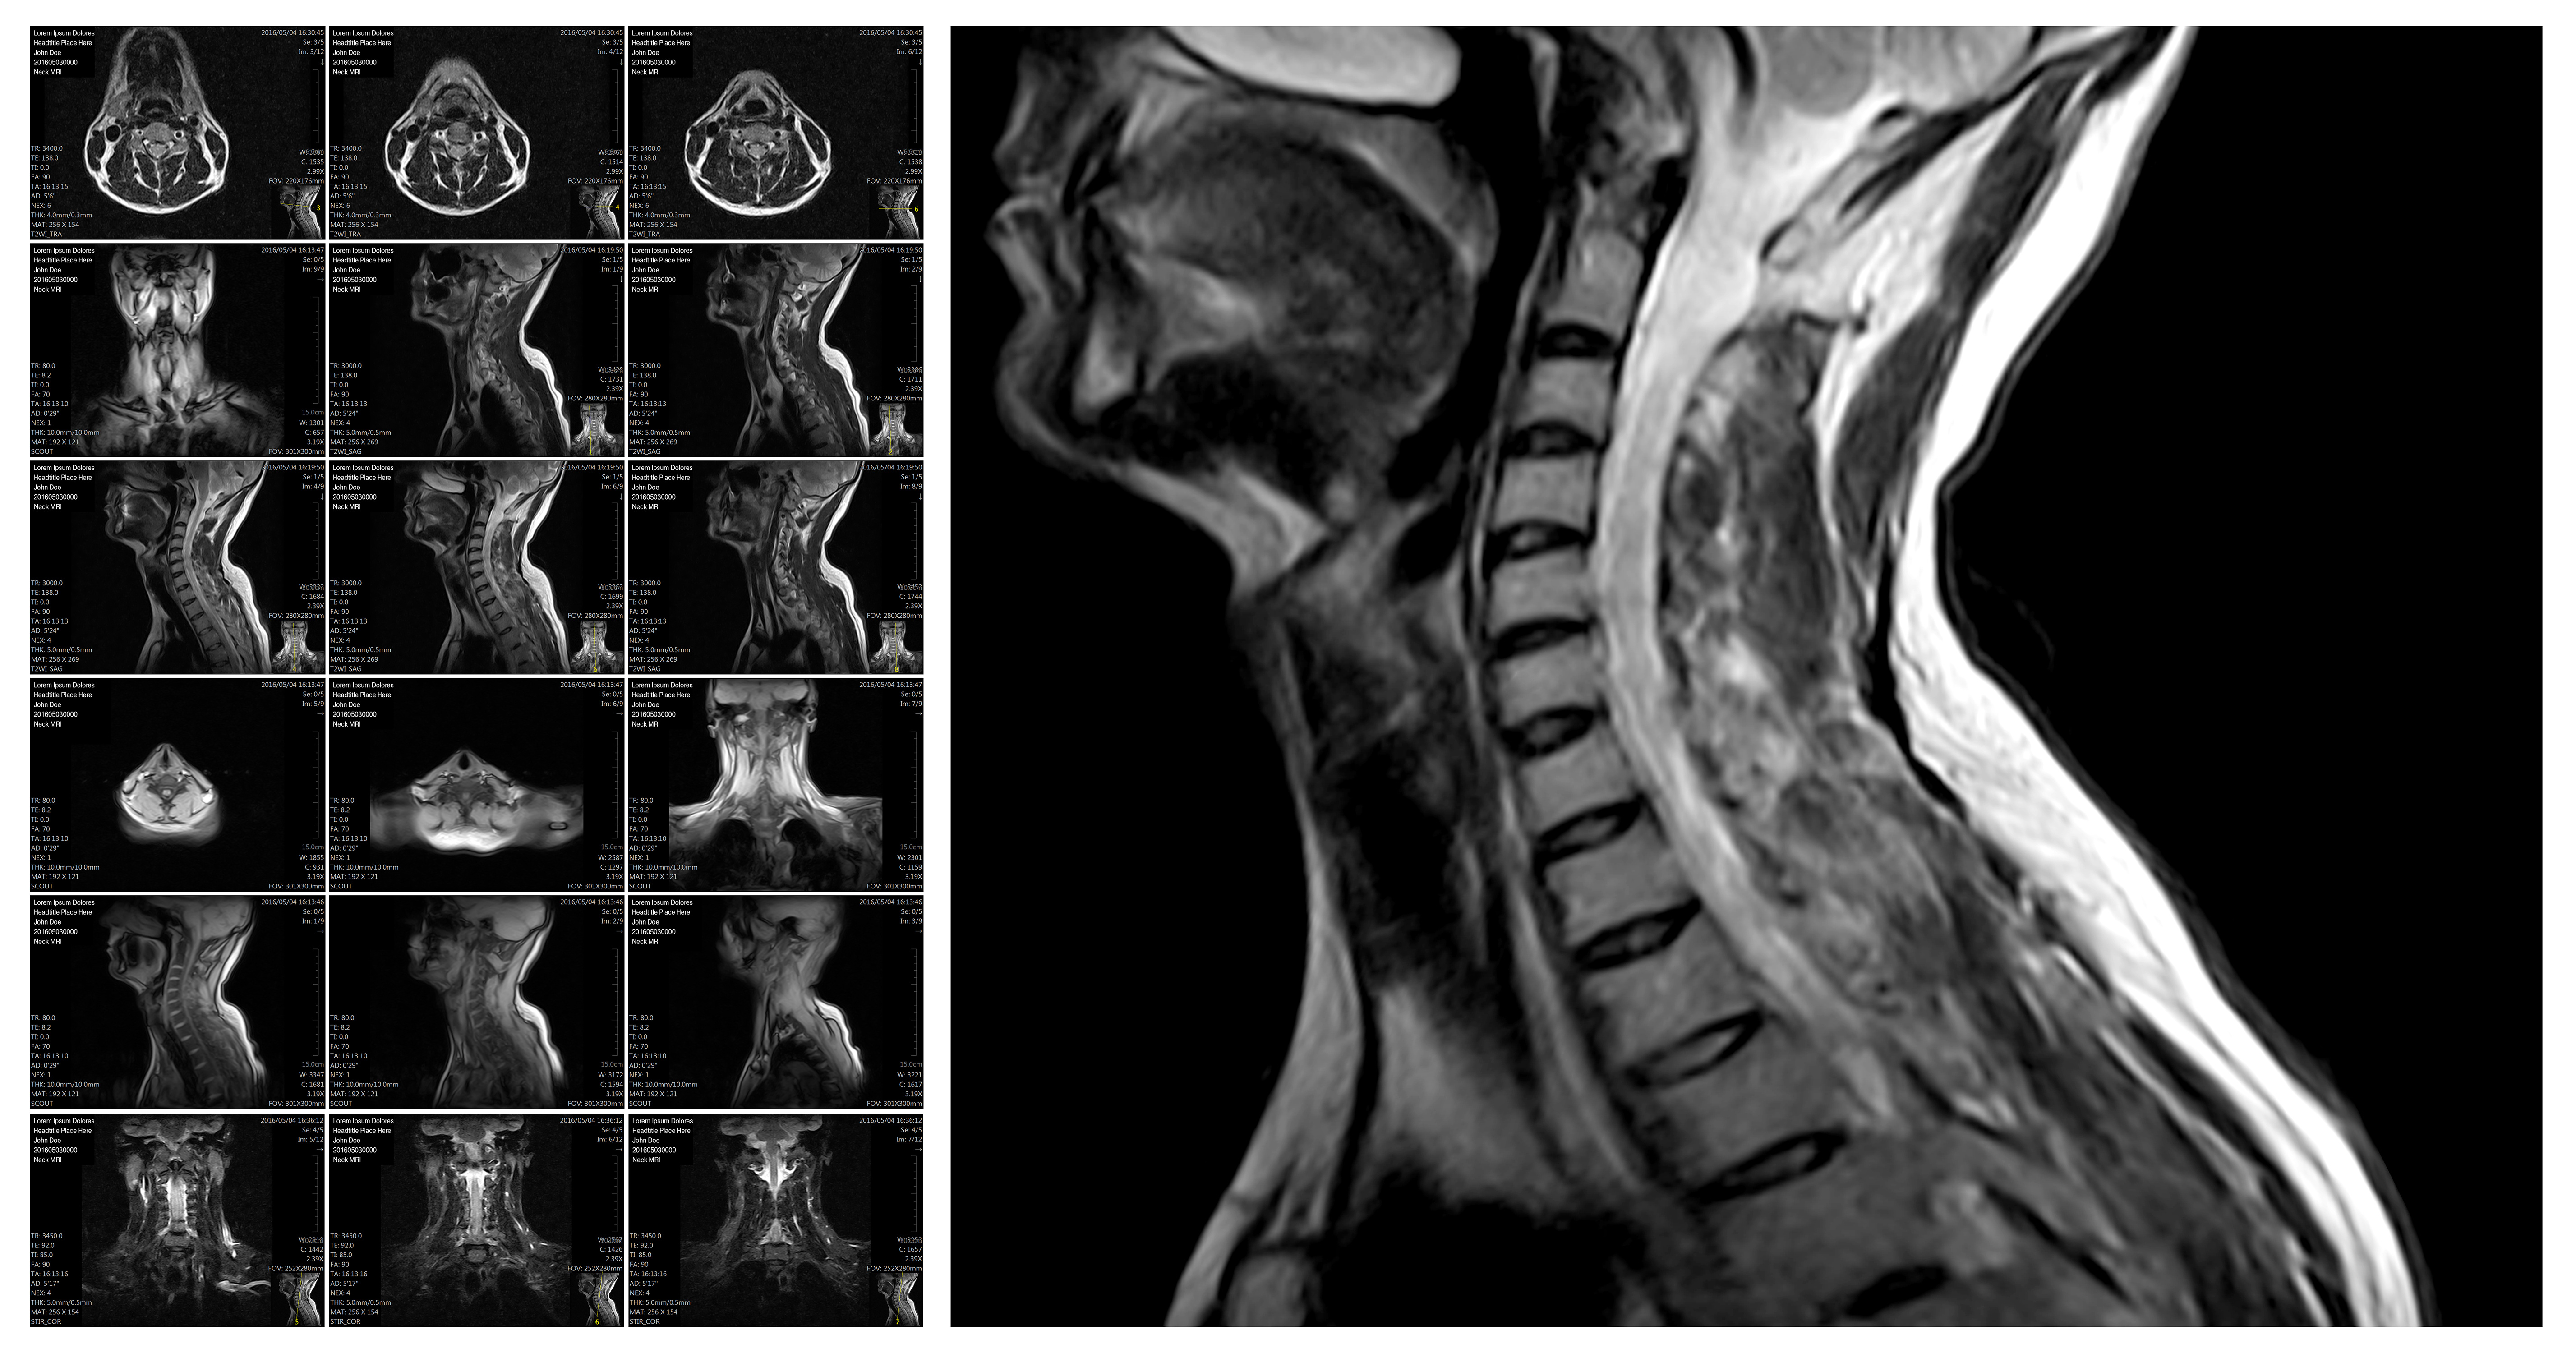

The future of spine surgery starts here.

At SCOLI, we are doing what's never been done. From groundbreaking treatments to personalized care enhanced through innovations like AI and 3D printing, we have the skills, the people, and the ideas to transform medicine. Health care will never be the same.

Pioneering Modern Spine Endoscopy in Western PA

Leading the advancement of minimally invasive spine surgery through cutting-edge endoscopic techniques in Western Pennsylvania.